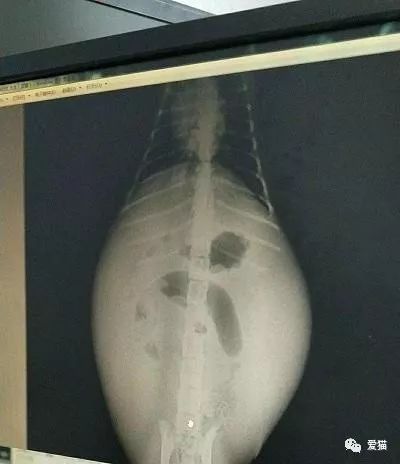

我们前面说到,传腹是因为冠状病毒离开肠道,入侵了其他器官组织,当这些器官组织感受到此病毒的威胁时,免疫系统就会做出过度的反应,然后释放出一些混杂着蛋白质、白细胞和血浆的粘液,储藏在猫咪的肚子里。

所以湿性传腹的猫咪肚子一般都会异常的大。

4.湿性传腹的猫咪肚子会肿胀无比